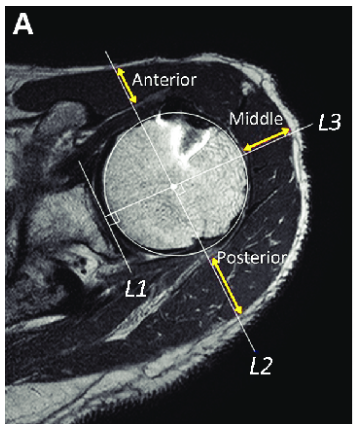

The deltoid muscle, comprising the anterior, lateral, and posterior heads, is one of the most crucial muscles for achieving a well-rounded and balanced shoulder appearance. However, there’s a common misconception that needs to be clarified: when you view the shoulder from the side, much of the visible muscle mass is mistakenly attributed solely to the lateral (side) deltoid head. In reality, a significant portion of that mass includes contributions from the anterior and posterior deltoid heads.

Section 1: Anatomy of the Deltoid Muscle

The deltoid muscle is a triangular-shaped muscle that covers the shoulder joint, allowing for a wide range of movements. It is divided into three heads:

- Anterior (Front) Deltoid: This head originates from the clavicle and is primarily responsible for shoulder flexion, internal rotation, and horizontal adduction. It is heavily involved in pressing movements, such as the bench press and overhead press.

- Lateral (Side) Deltoid: The lateral deltoid originates from the acromion and is the main muscle responsible for shoulder abduction, which is the movement of lifting the arm away from the body. It’s typically targeted with exercises like lateral raises.

- Posterior (Rear) Deltoid: This head originates from the spine of the scapula and is responsible for shoulder extension, external rotation, and horizontal abduction. Exercises like reverse flyes and face pulls target the posterior deltoid.

Section 2: The Side View Misconception

When viewed from the side, the shoulder’s rounded appearance is not due to the lateral deltoid alone. In fact, a substantial portion of what you see is the anterior and posterior deltoid heads wrapping around the shoulder joint. This anatomical overlap means that people often overestimate the mass of the lateral deltoid when, in reality, much of the visible muscle mass from this angle belongs to the front and rear deltoids.